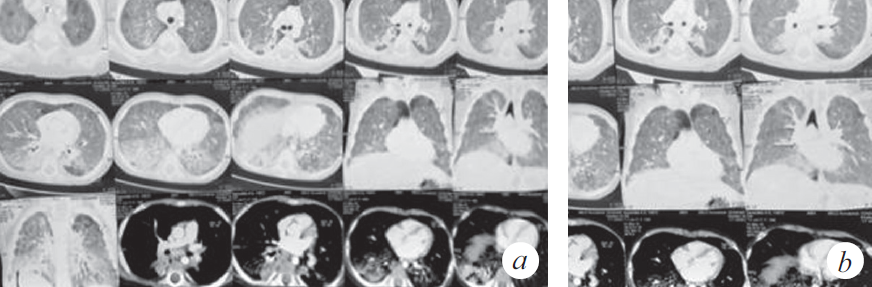

Из анамнеза заболевания известно, что 01.11.2018 ребенок по неосторожности родителей принял внутрь парафиновое масло. Мама стимулировала рвоту, после чего ребенок стал подкашливать. Бригадой скорой медицинской помощи девочка доставлена в стационар по месту жительства с диагнозом: «Острая респираторная вирусная инфекция, ларинготрахеит». О факте случайного приема парафинового масла и стимуляции рвоты мать не сообщила. Первые три дня пациентка находилась в стационаре (детская клиническая больница № 1) и, учитывая улучшение, была выписана под наблюдение участкового врача. На одиннадцатый день заболевания девочка с симптомами внебольничной двусторонней пневмонии была госпитализирована в стационар центральной клинической больницы СО РАН, с дальнейшим переводом в инфекционную больницу. По результатам компьютерной томографии (КТ) органов грудной клетки констатированы признаки диффузного интерстициального заболевания легких (рис. 1). На этом основании заподозрено аспирационное поражение паренхимы легких, вероятность которого подтвердила мать при дополнительном сборе анамнеза.

Рис. 1. Компьютерная томограмма органов грудной клетки (через 3 нед. от дебюта заболевания) (a). Признаки диффузного интерстициального заболевания легких, вероятно, двусторонняя липоидная пневмония, дифференциальный диагноз с альвеолярным протеинозом (b)

Fig. 1. CT scan of the chest (3 weeks after the onset of the disease) (a). Signs of diffuse interstitial lung disease, probably bilateral lipoid pneumonia, differential diagnosis with alveolar proteinosis (b)

Через 2 нед. госпитализации в ОРИТ у ребенка наросли клинические и параклинические проявления госпитальной пневмонии (лихорадка, повышение С-реактивного белка до 39,7 мг/л), высев грибов рода Candida, Staphylococcus aureus — из верхних дыхательных путей; Еnterococcus faecalis, Еnterococcus fecuim, Klebsiella pneumoniae — из мочи, кала. На контрольной КТ: отрицательная динамика в виде увеличения консолидации в периферических отделах легких (рис. 2), клиническая картина не изменилась. На фоне антибактериальной терапии широкого спектра действия дыхательная недостаточность не прогрессировала, явления инфекционного токсикоза были купированы, кашель отсутствовал. Максимальная оценка по шкале SOFA (Sequential Organ Failure Assessment) 3 балла.

Рис. 2. Компьютерная томограмма органов грудной клетки (через 5 нед. от дебюта заболевания) (a). Признаки диффузного интерстициального повреждения легких. Отмечена отрицательная динамика в виде увеличения консолидации в периферических отделах легких (b)

Fig. 2. CT of the chest organs (5 weeks after the onset of the disease) (a). Signs of diffuse interstitial lung disease. Negative dynamics in the form of increased consolidation in the peripheral parts of the lungs (b)